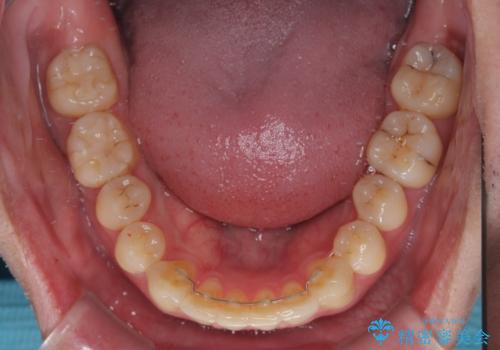

お仕事が忙しく、1日の装着時間は不十分となる日もありましたが、治療は順調に進めていくことができました。

途中、以前大きなむし歯で処置をした歯が痛み出し、根管治療が必要となったため、根管治療とオールセラミッククラウンによる補綴治療を行い、その後にインビザラインによる仕上げの歯列移動を行い、無事に治療を終えることができました。